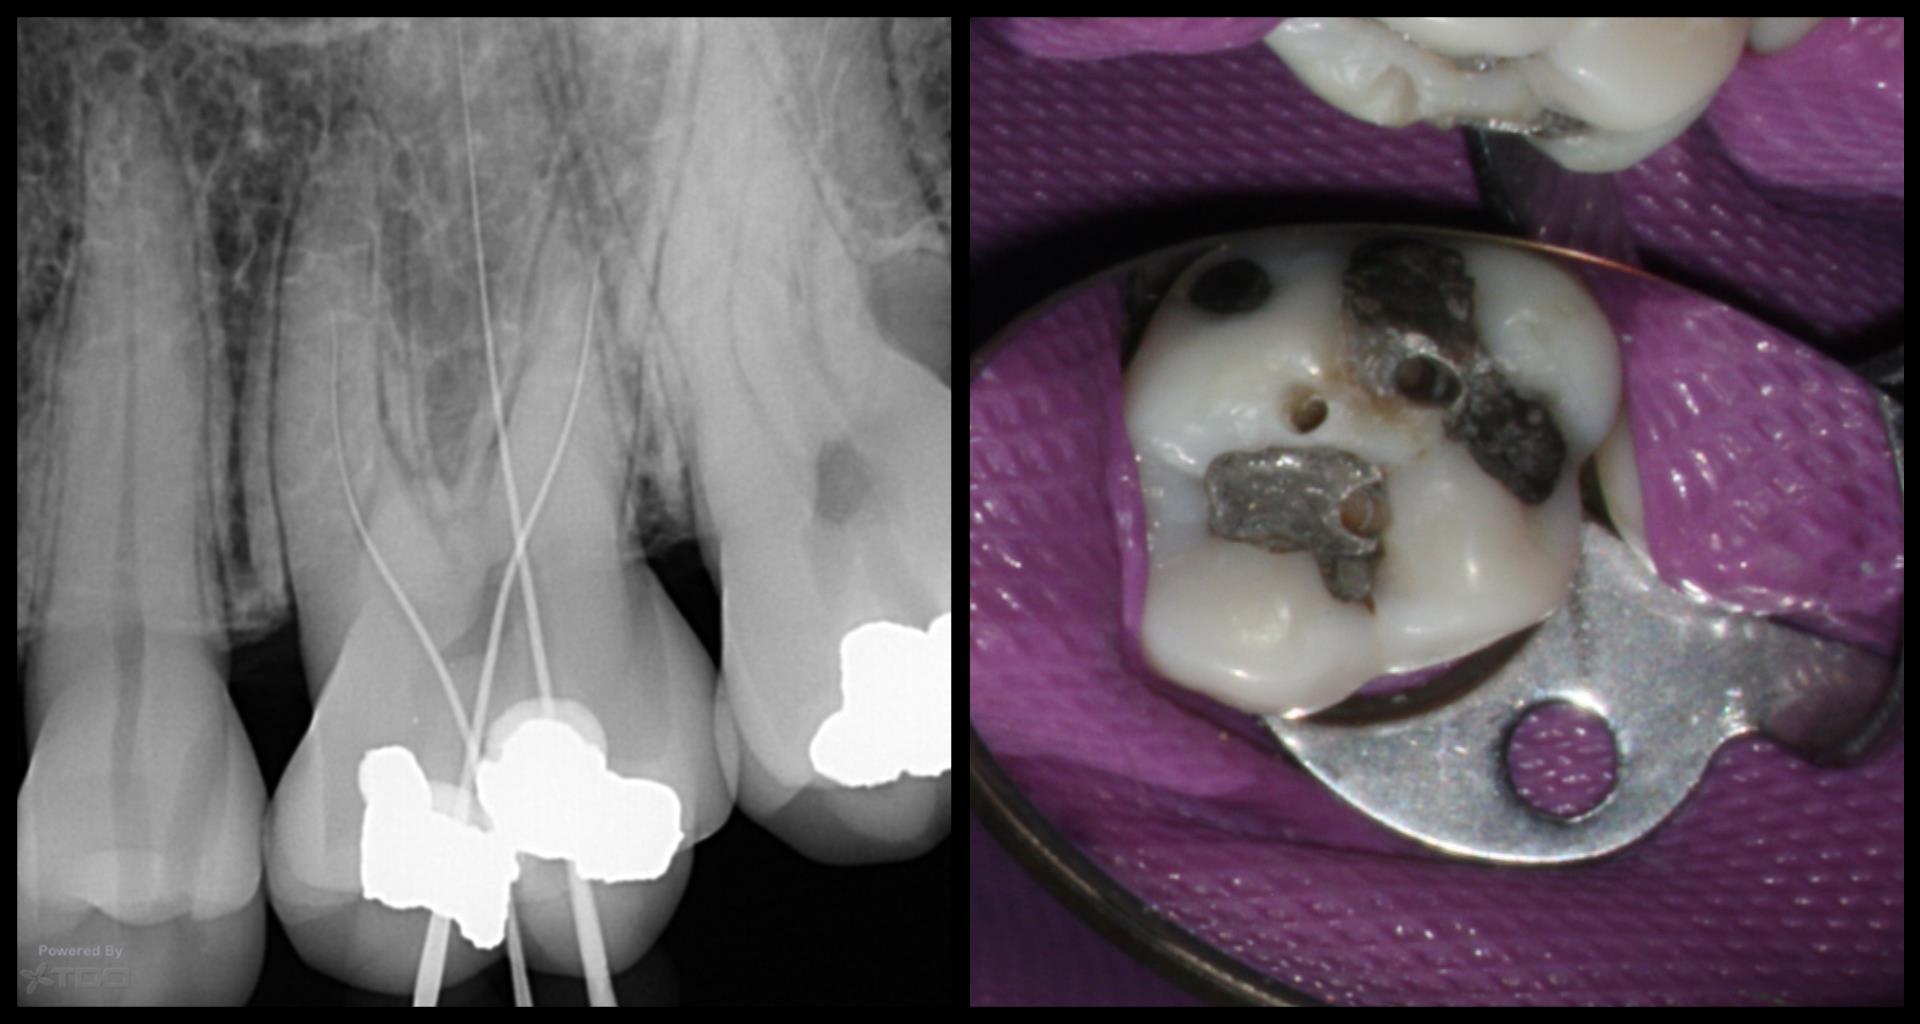

This was done on a cadaver just as an exercise to practice the X-nav technique and to test its accuracy. Look at the video to understand better if this doesn’t make sense.

This was done on a cadaver just as an exercise to practice the X-nav technique and to test its accuracy.

Look at the video to understand better if this doesn’t make sense.